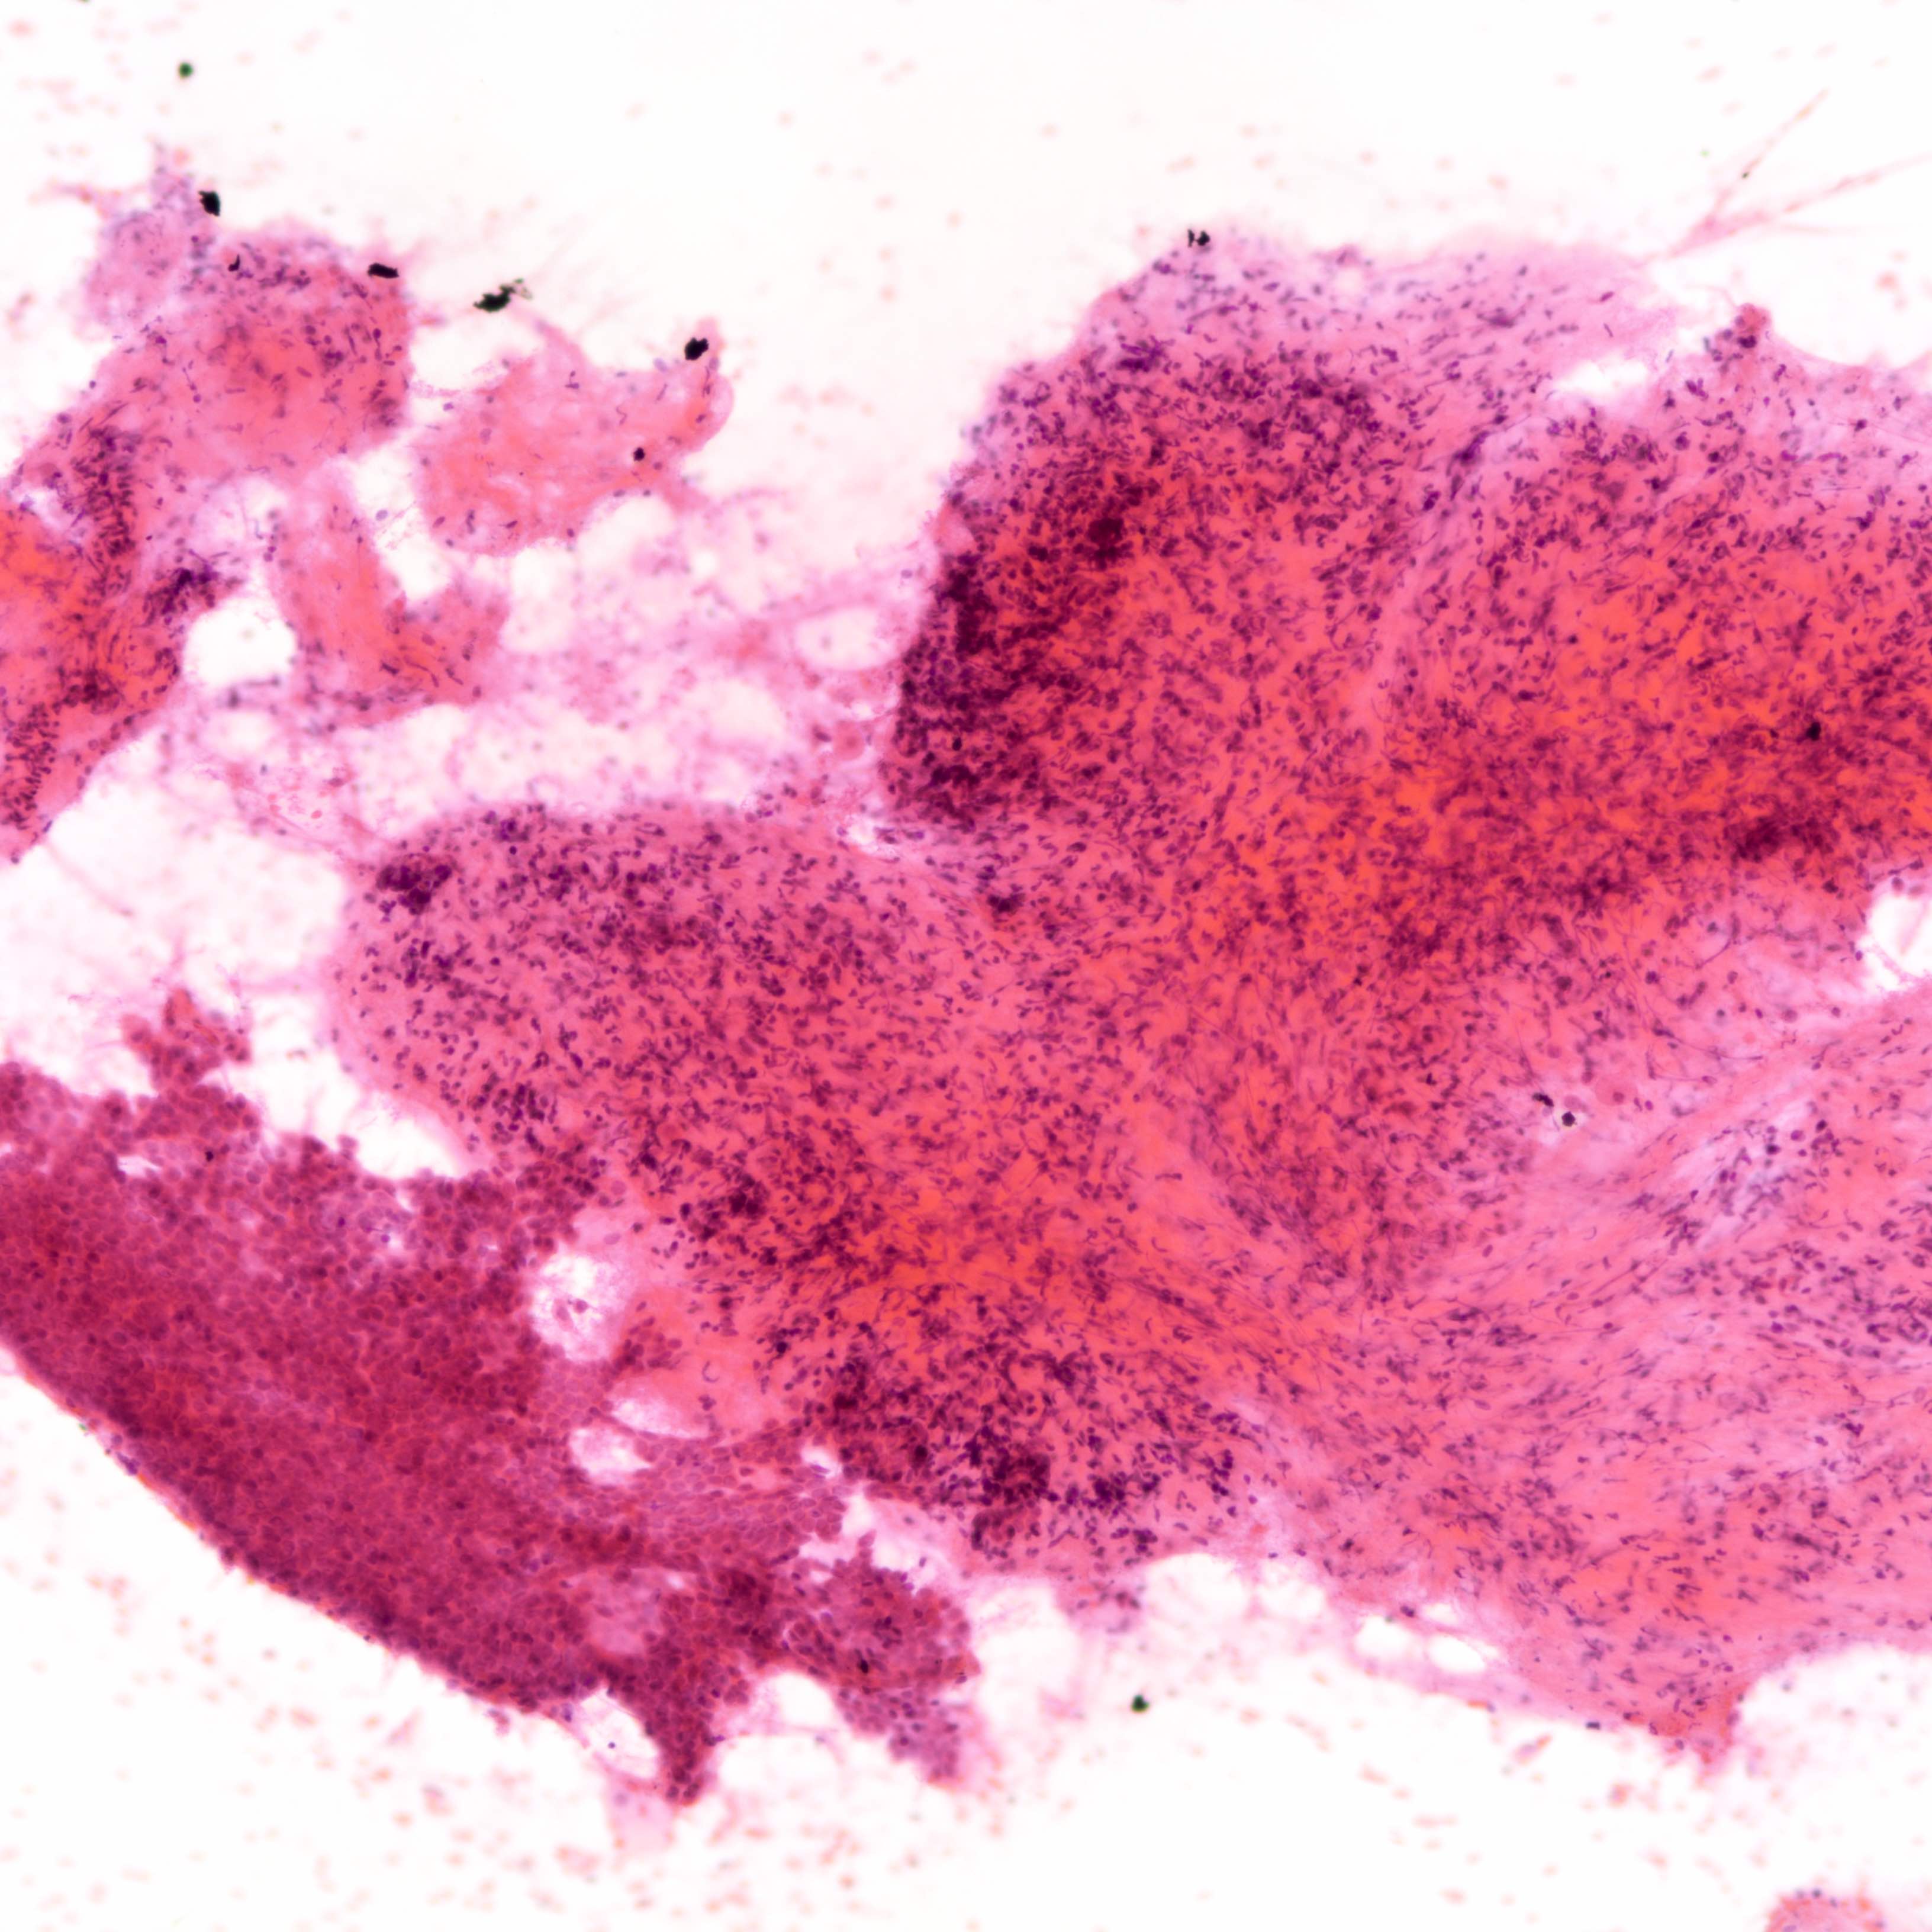

Cytology description

- Fibromyxoid stromal clumps

- Reduced epithelial stromal ratio compared with fibroadenomas

- Higher nuclear atypia and cellularity in phyllodes tumor of higher grades

- Large wavy and folded epithelial clusters

- Usually exhibits benign cytomorphology

- Occasionally, hyperplastic changes with enlarged and vesicular nuclei and small visible nucleoli may be seen

- Fibroblastic pavements

- Increased atypia in dispersed cells in phyllodes tumor of higher grades (Cancer Cytopathol 2010;118:33)

- Multinucleated tumor cells and marked stromal anaplasia reported in malignant phyllodes tumor (Cancer Cytopathol 2010;118:33)

Cytology images

Contributed by Joshua J.X. Li, M.B.Ch.B. and Gary M. Tse, M.B.B.S.

Malignant phyllodes tumor